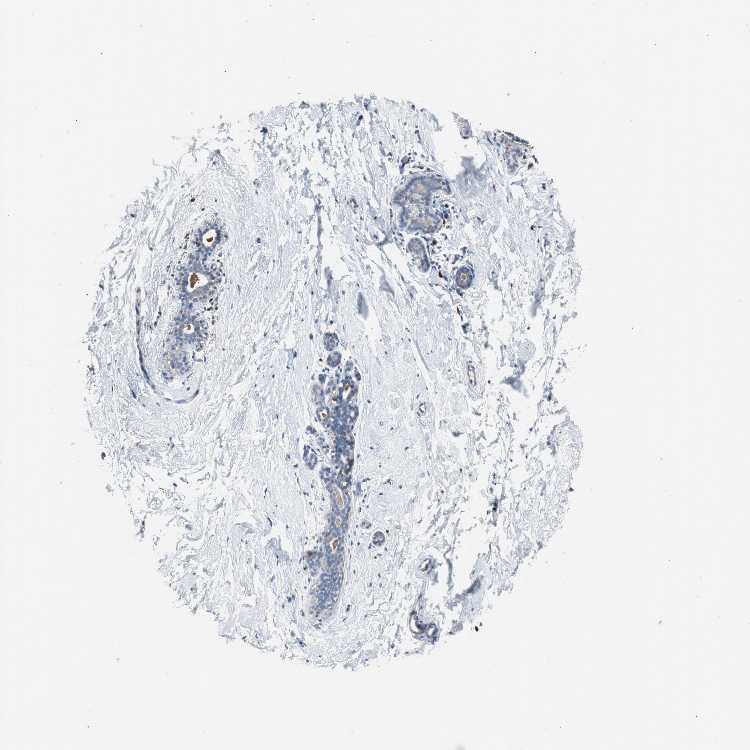

BREAST - Antibody stainingi

Antibody staining in the annotated cell types in the current human tissue is reported as not detected, low, medium, or high, based on conventional immunohistochemistry profiling in selected tissues. This score is based on the combination of the staining intensity and fraction of stained cells.

Each image is clickable and will lead to virtual microscopy that enables deeper exploration of all samples and also displays staining intensity scores, fraction scores and subcellular localization as well as patient and tissue information for each sample.

Antibody HPA002327Antibody HPA006040Antibody CAB022160

Adipocytes -LowNot detected

Glandular cells Not detectedLowNot detected

Myoepithelial cells Not detectedNot detectedNot detected